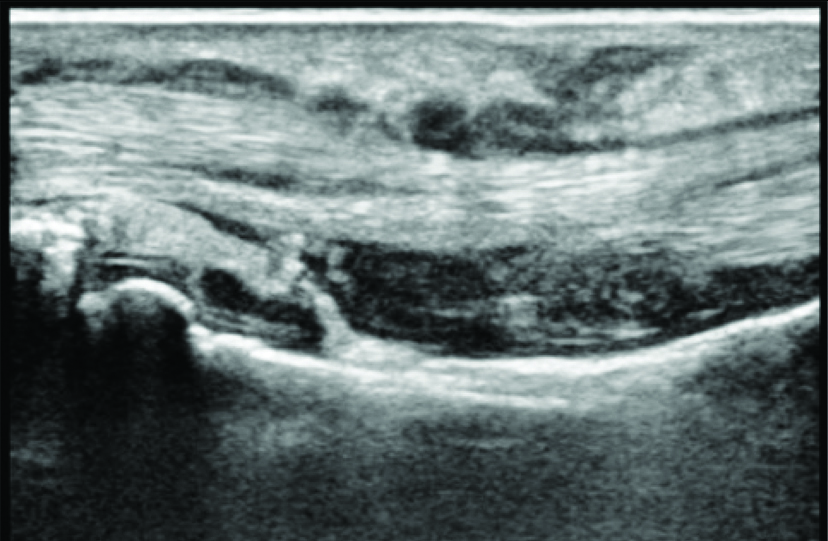

On ultrasound evaluation, normal flexor tendon appears hyperechoic, uniform in thickness and echogenicity with fibrillar echopattern [Table/Fig-1]. Synovial sheath of the tendon appears as thin hypoechoic halo surrounding the tendon seen in longitudinal and transverse planes. Tenosynovitis was observed as thin or thick layer of synovial membrane with or without associated fluid and increased vascularity which can be detected as foci of increased doppler activity on color or power doppler [Table/Fig-2a,b]. Earliest marker of tendon damage is loss of fibrillar echopattern which is unique quality of normal tendon. Partial or full thickness tendon tears are defined as interruption of tendon fibers with or without hypoechoic material filling the defect [9].

Ultrasonography of normal flexor tendon appearing hyperechoic, uniform in thickness and echogenicity with fibrillar echopattern.